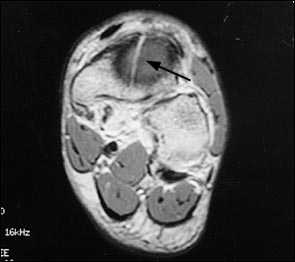

МРТ является вторым по сенситивности исследованием и становится альтернативой сцинтиграфии. Отёк кости на Т-2 взвешенных изображениях обнаруживает костные изменения предшествующие перелому. МРТ нецелесообразно выполнять если уже выполнены сцинтиграфия и КТ.